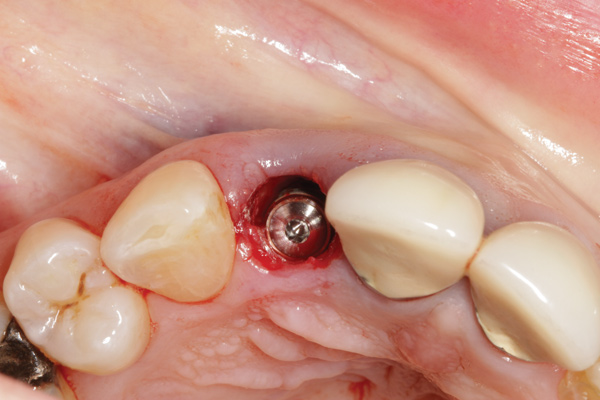

When placing an implant in the esthetic zone, ideal 3-dimensional positioning, including mesio-distal, apico-coronal, and orofacial dimensions, is essential to achieve favorable esthetic outcomes, regardless of the implant system used (Figure 6).45 With respect to the orofacial dimension, implants should be placed in a more palatal or lingual position to allow the presence of at least 2 mm of buccal bone thickness from the implant buccal shoulder.45,46 When the distance of the buccal bone wall and implant buccal shoulder is < 2 mm, a significantly higher incidence of midfacial recession has been previously reported.3,12 Placement of bone graft (Figure 7) and immediate restoration (Figure 8 and Figure 9) at the time of implant placement has also been suggested to increase peri-implant soft-tissue height and thickness.51 In the apico-coronal dimension, the implant head should be at least 3 mm apical to an imaginary line connecting the CEJ of the adjacent teeth and 1 mm to 2 mm apical to the interproximal and crestal bone to ensure a proper implant emergence profile and facilitate proper implant restoration (Figure 10). Regarding the horizontal implant–tooth distance, implants should be placed no closer than 1.5 mm from the adjacent root surface to minimize resorption of the interproximal alveolar crest, which causes a reduction in the papillary height.46,52